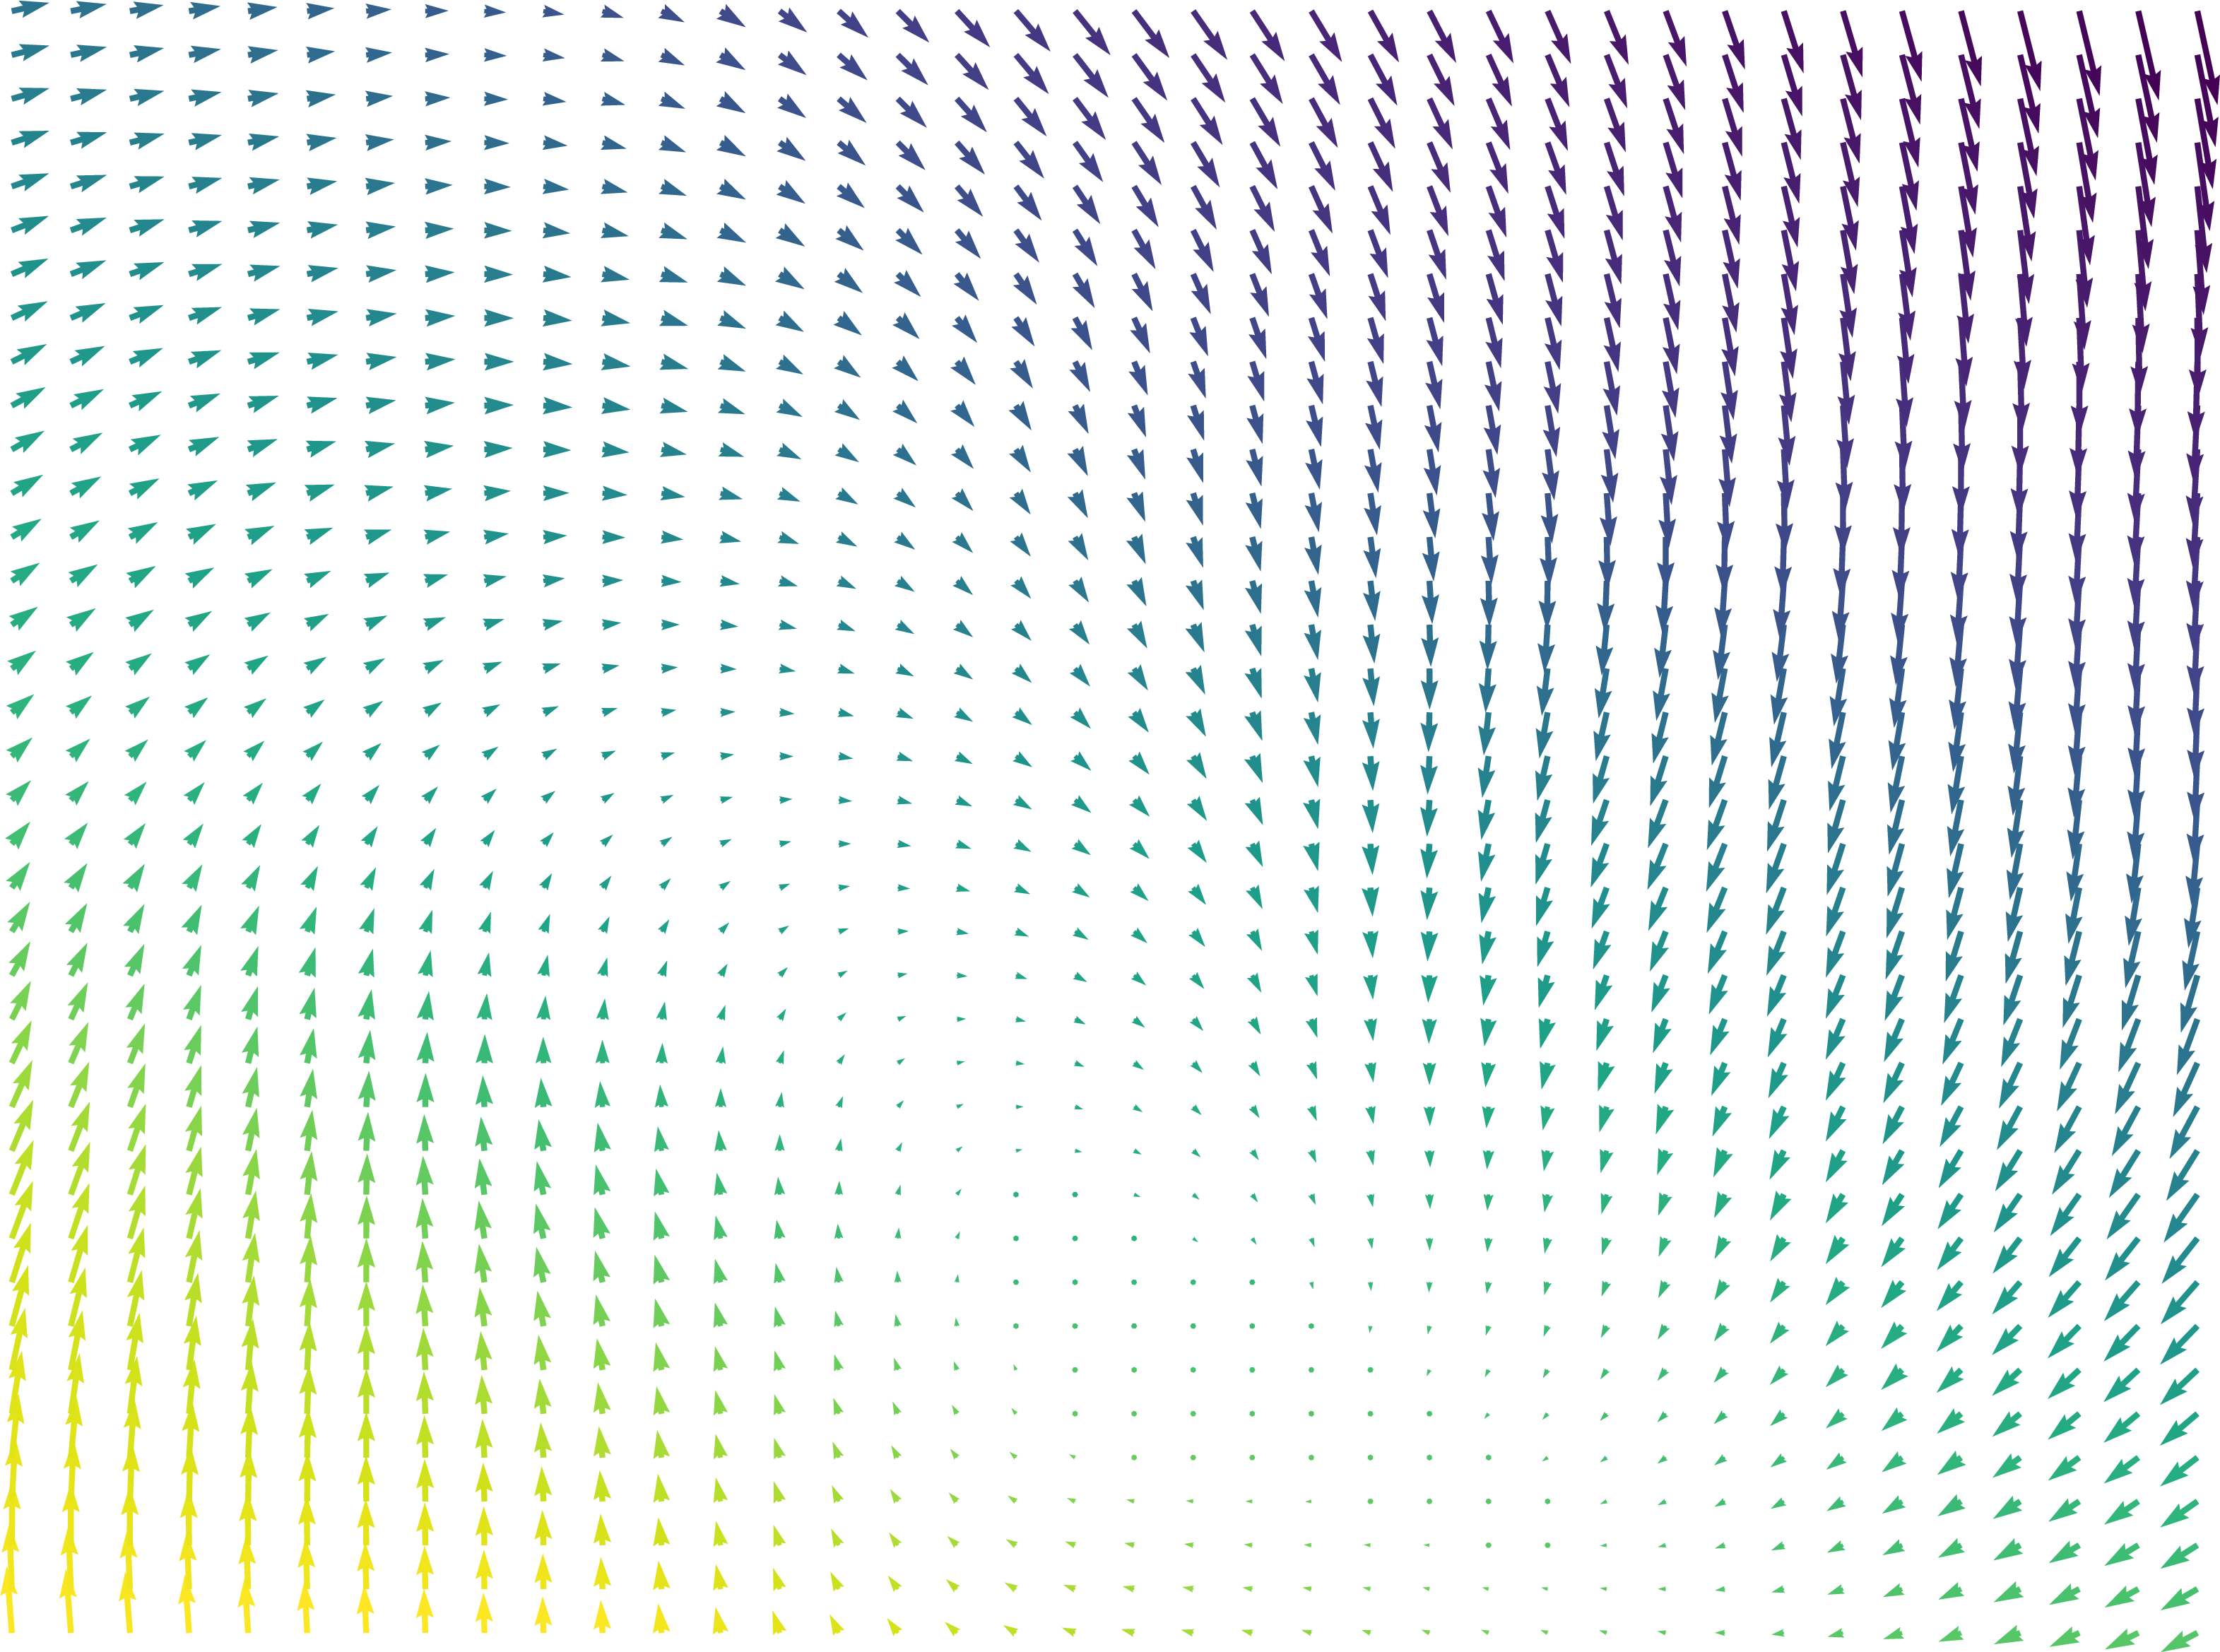

To motivate our work, consider the example in Fig. 1, in which we performed a 3D registration of two MRI brain scans from the OASIS [7] dataset using the popular Stationary Velocity Field (SVF) approach [8, 9, 10] and our proposed method (denoted ). In the first example, the sought deformation is comparably small before the registration process, and both approaches perform equally well. In the second example, the deformation includes a larger rotational component. When looking at the deformed images only, the SVF approach appears to generate an alignment that is clearly worse, but not catastrophically so. This is deceptive: inspecting the generated deformation fields (Fig. 2), it becomes clear that the SVF approach generates a deformation that – while it maps corresponding intensity values reasonably well between the images – is far from the ground truth.

The findings on these (synthetic) examples are compatible with our perception of the existing literature: In general, we found that SVF-based approaches mostly seem to be applied to pre-aligned images, and/or that the judgement of their accuracy is solely based on the similarity of the images after registration or on related proxies, such as the overlap of known segmented regions, that do not necessarily imply sensible deformation fields.

This behavior is clearly visible in Fig. 1 and Fig. 2 shown in the introduction, in which the resultant images as well as an exemplary slice of the deformation field are depicted under small and large deformations. It illustrates how the matrix group approach is able to capture even large rotational deformations, whereas the use of an SVF tends to align the intensity values by local deformations instead of a global rotation, resulting in the large RMSE observed in Fig. 12.